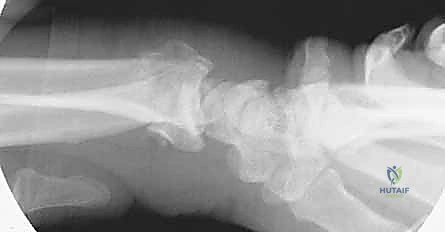

- الأشعة السينية (X-rays): بأوضاع متعددة لتقييم زوايا الكسر ومقدار الانهيار العظمي.

مبدأ عمل الصفيحة الجسرية (Distraction Ligamentotaxis)

تعتمد هذه التقنية المتقدمة على مبدأ إبقاء المفصل مشدوداً ومثبتاً من الخارج. الصفيحة تعمل كـ "جسر" يعبر فوق منطقة الدمار الشامل في العظم، وترتكز على عظم سليم في الساعد وعظم سليم في اليد. هذا الجسر يمنع العظم المفتت من الانهيار ويسمح للشظايا الصغيرة بالالتئام في مكانها الصحيح بفضل الشد الطبيعي للأربطة المحيطة.

3. إدخال الصفيحة الجسرية (Plate Insertion)

بمهارة فائقة، يتم تمرير الصفيحة المعدنية المصنوعة من التيتانيوم تحت الجلد وفوق الأوتار عبر الشقين، بحيث تعبر مفصل الرسغ بالكامل متجاوزة منطقة الكسر المفتتة دون العبث بها.

يتم تثبيت الصفيحة بقوة باستخدام براغي متطورة (Locking Screws) في عظم الساعد السليم وعظم المشط في اليد. هذه البراغي تلتحم بالصفيحة لتشكل هيكلاً صلباً للغاية لا يتأثر بالحركة.

أثناء العملية، يستخدم الدكتور هطيف جهاز الأشعة المباشر للتأكد من المحاذاة المثالية للعظم واستعادة الطول والزوايا التشريحية الصحيحة للرسغ.